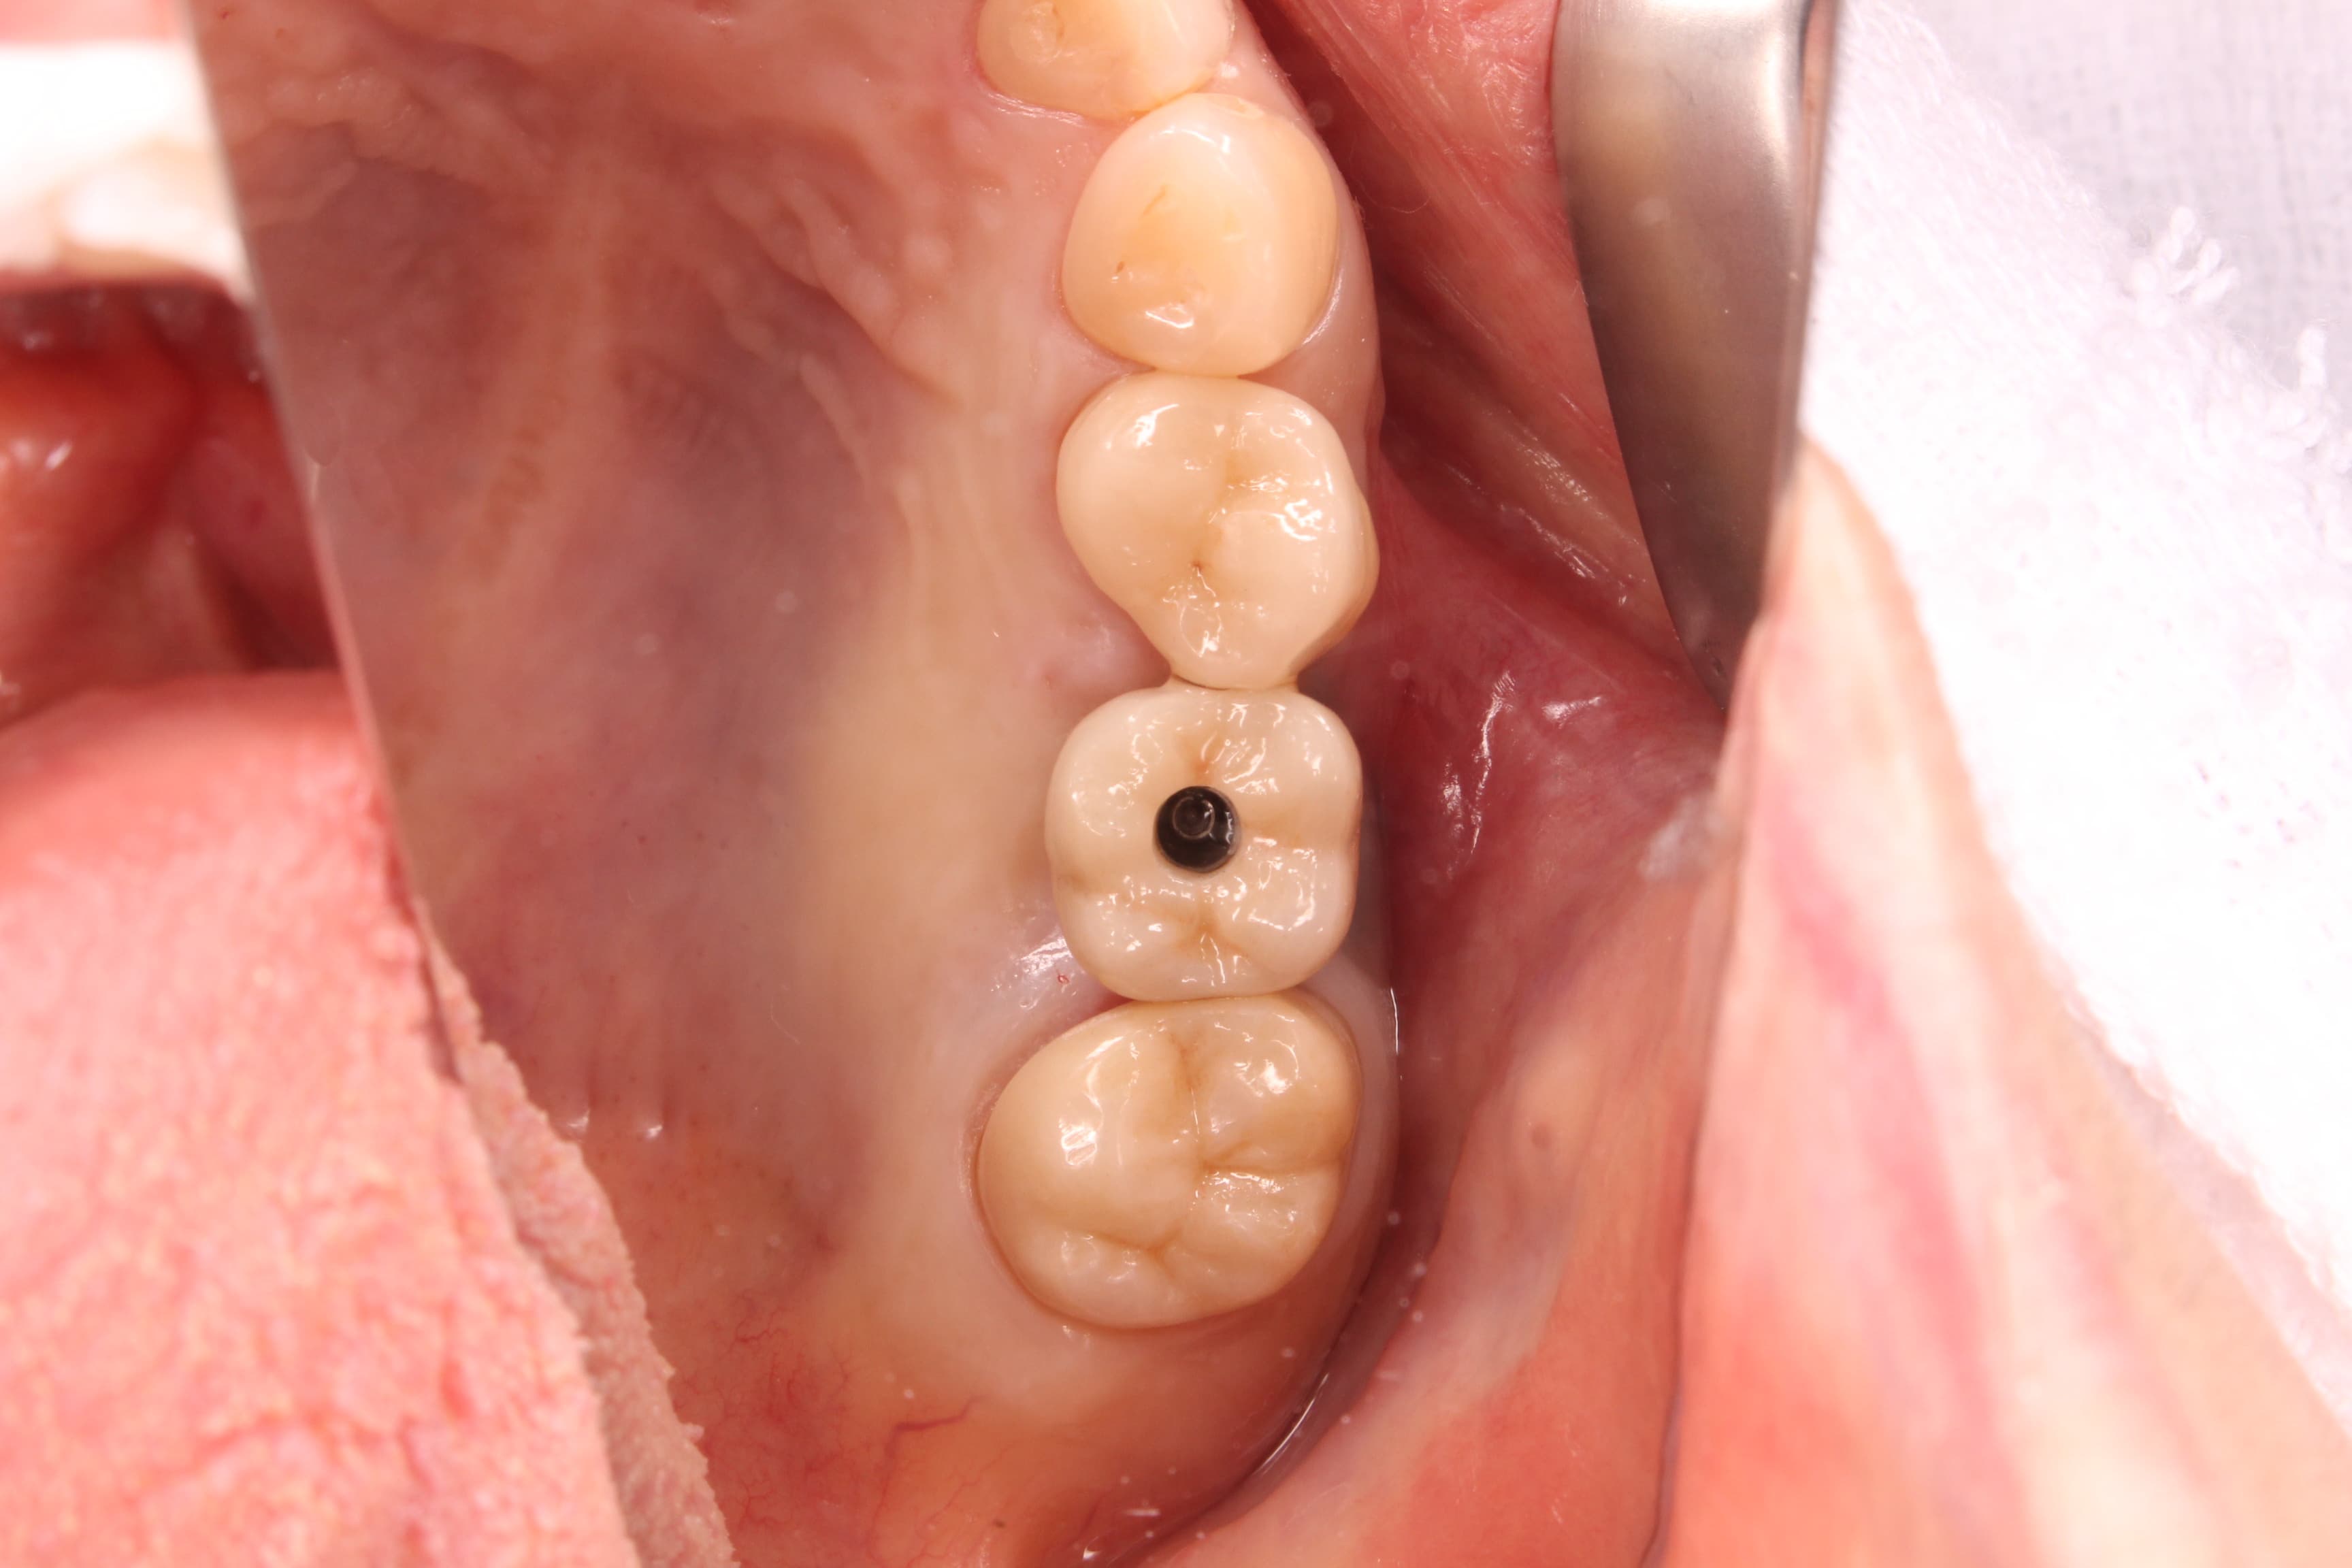

治療後の状態⇩

インプラントの上部構造は、スクリューリテインと言われるネジで固定する方法をとっています。中央部分にアクセスホールがありますが、ここはレジン(樹脂)で塞いでいます。

何か問題が出た場合は、この樹脂を取り除き、ネジを緩めて上部構造を外します。